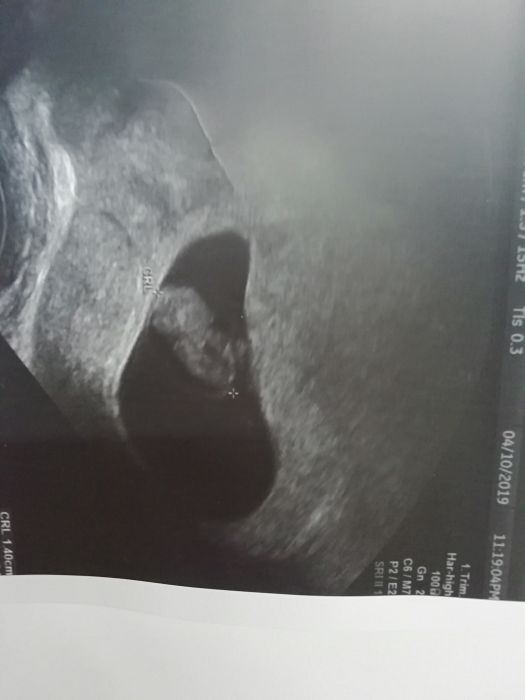

Děvčata teď jsme se vrátili z pohotovosti. Začala jsem spinit. No ten strach byl hrozný. V nemocnici ani znamky po špinění. Dle UTZ mimisek v pořádku a za týden vyrostl a 0,5 cm. Srdíčko tlouklo a pěkně nám s paní doktorkou mával ručičkama. Prý je těhotenství velmi dobře založeno a špinění se někdy objeví. No je to naše vymodlene mimisko tak jsme nechtěli nic podcenit. Ať jste všechny v pořádku a podávejte průběžně info